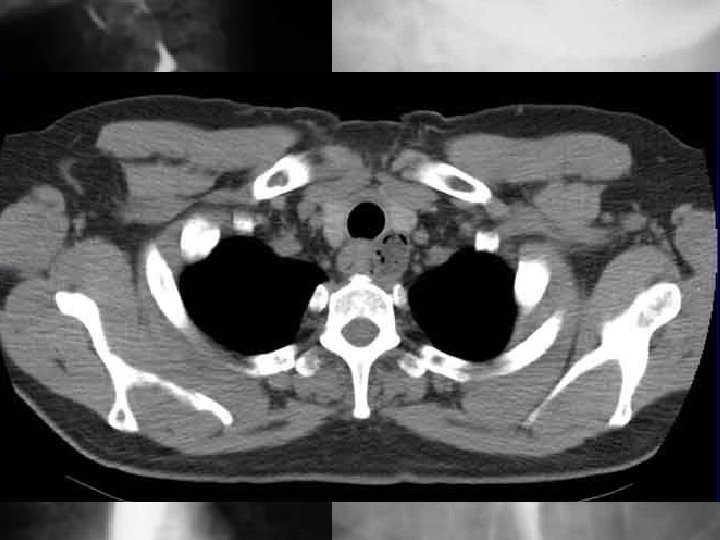

Large intestine - examination • Hemocult – hidden bleeding examination • endoscopy – rectoscopy (rigid), coloscopy (flexible) • X-ray- native, contrast - passage, irigography • CT